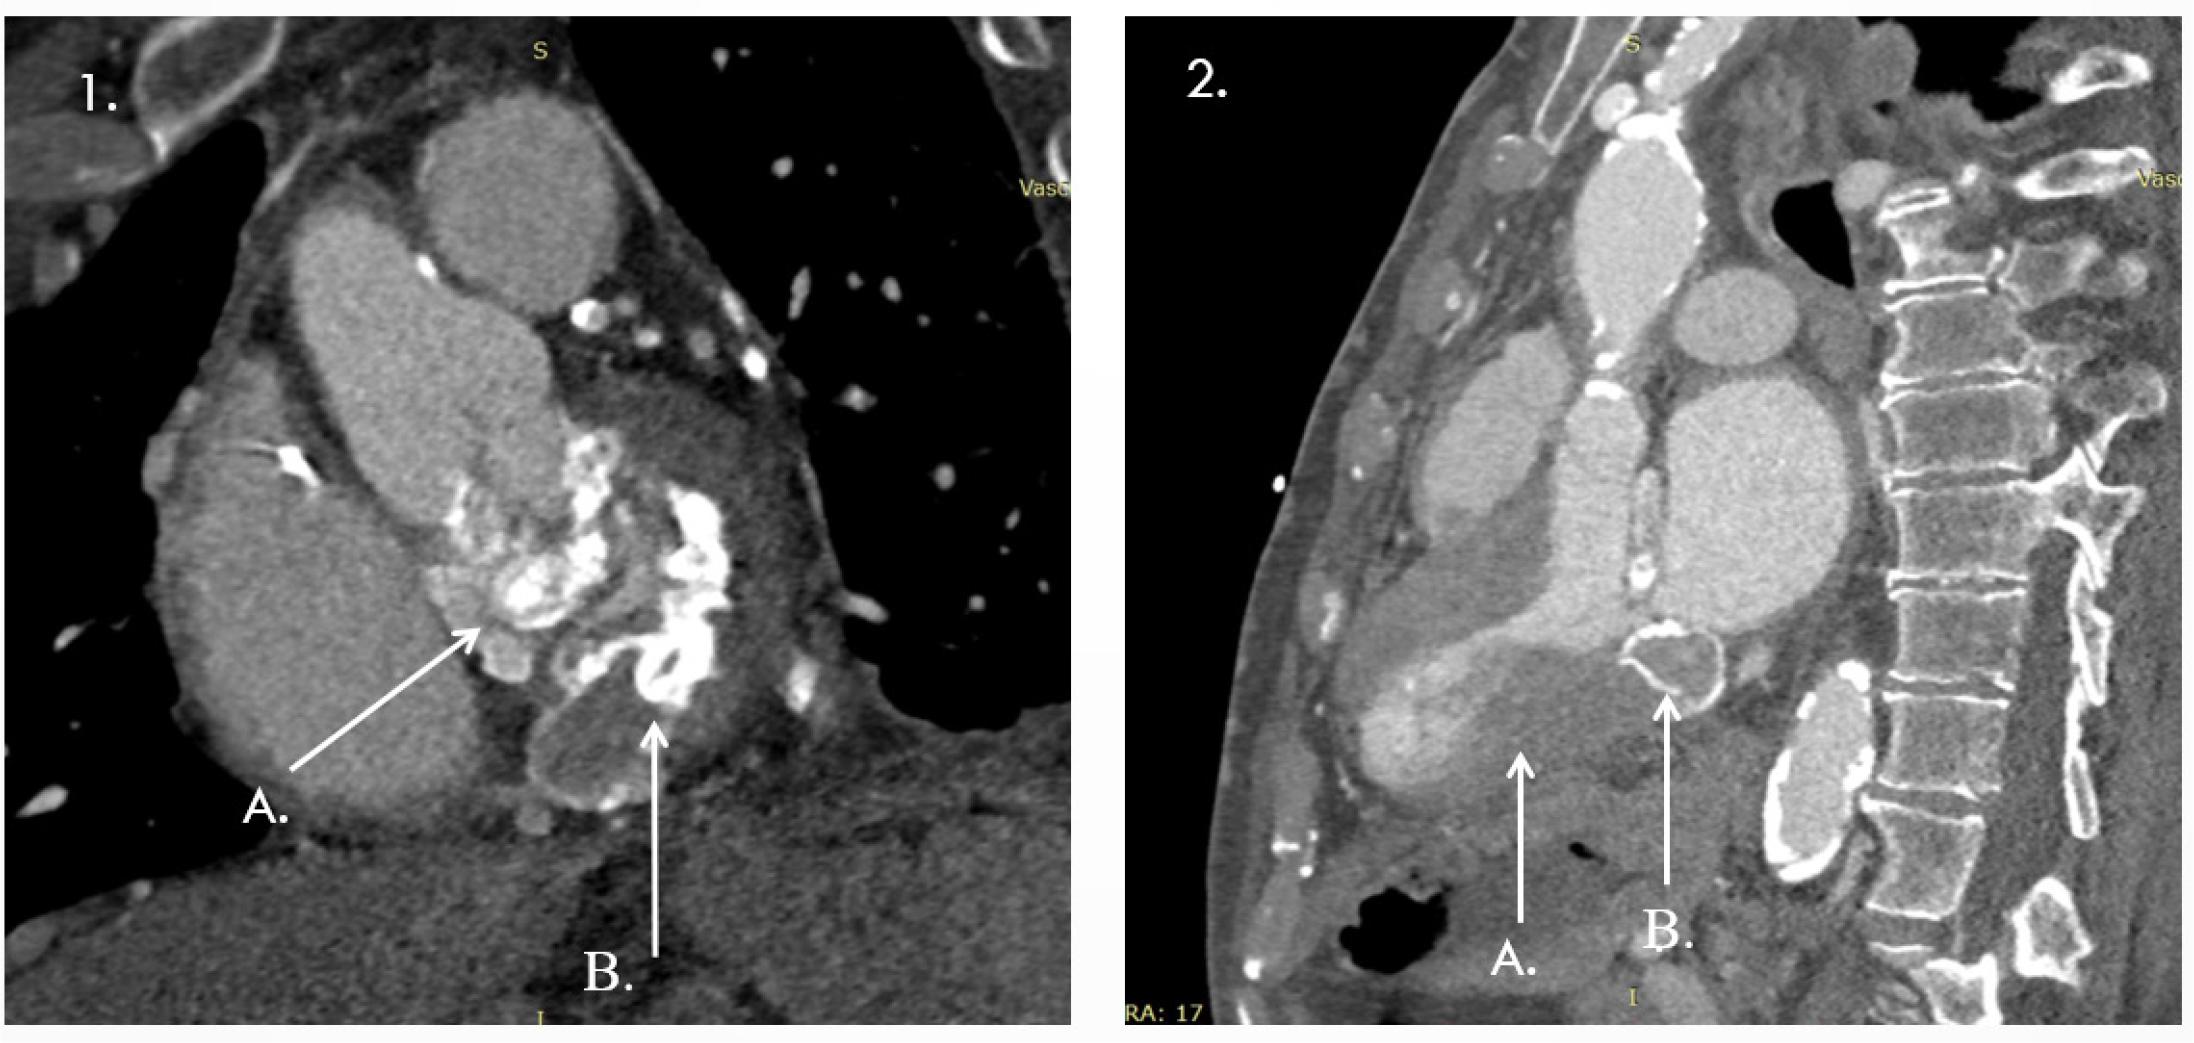

1 A, B Annular calcification extending to the mitral-aortic continuity and aortic root; 2 A-Important left ventricular hypertrophy; B-Toothpaste tumour.

A thoracic CT scan confirmed the temporary pacemaker lead at the right ventricular apex. It also showed extensive mitral annular calcification extending to the mitral-aortic continuity and aortic root, with two small cavitary defects (up to 30 mm), as well as vascular calcifications involving the aorta, supra-aortic trunks, and proximal coronary arteries (Summary Figure 3). Additional findings included distal SVC occlusion by a ~4 cm thrombus with a hyperdense peripheral component, likely a fractured catheter fragment. Another catheter fragment (35 × 6 mm) was identified in the left brachiocephalic vein with a thrombosed lumen and partial obstruction. Extensive thoraco-abdominal collateral venous circulation was noted. The left subclavian, brachiocephalic, jugular veins, and IVC were patent, though the proximal and mid-left subclavian vein showed stenosis, likely residual thrombus (Summary Figure 4).